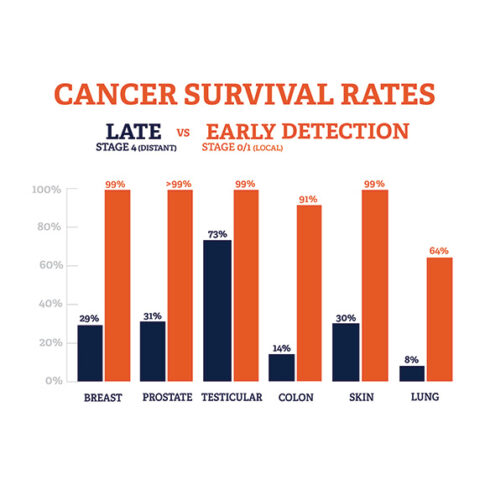

Data That Shows Early Detection Rather Than Late Detection In Breast Cancer